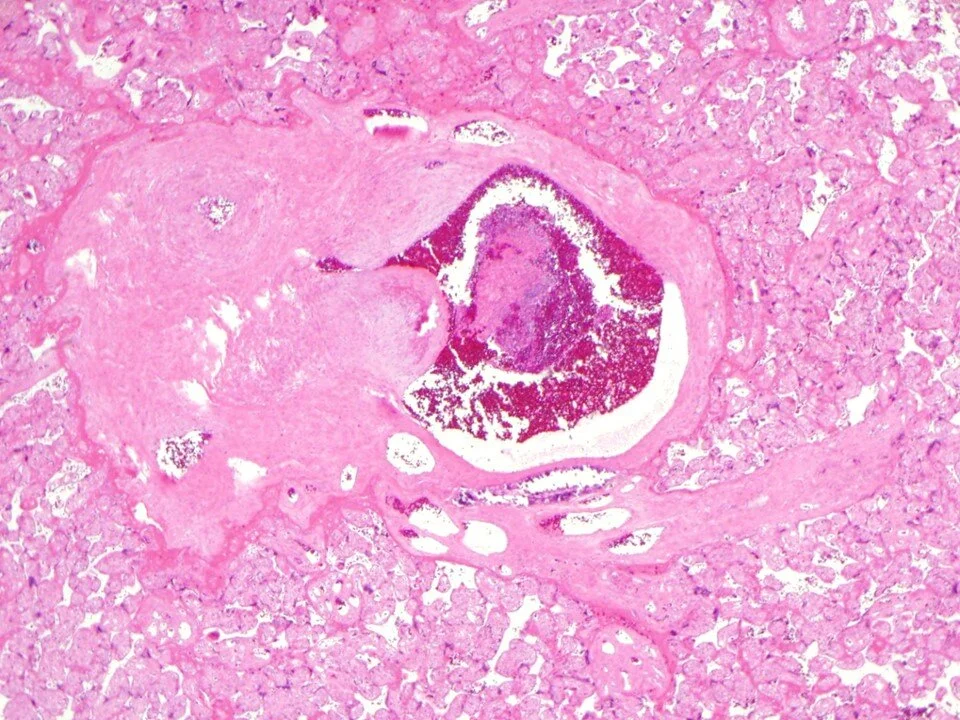

Chorionic vasculitis - inflammation involves chorionic plate vessels

Can be associated with placental abruption, umbilical cord occlusion, or difficult manual extraction